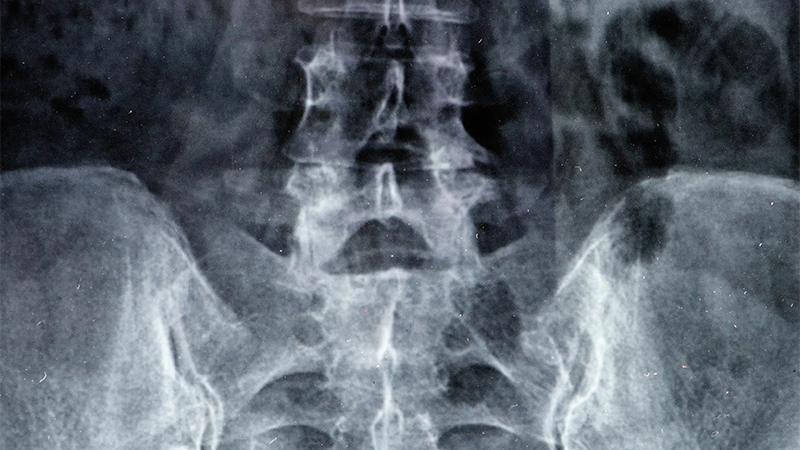

Diagnosis and Evaluation:

When assessing hip osteoarthritis, doctors take the patient’s history and perform a physical examination. They also examine the degree of pain and joint mobility. Imaging techniques such as X-rays, MRIs, or CT scans are often used to make a definitive diagnosis. These imaging techniques reveal the degree of arthritis, cartilage damage and osteophytes in the joint.